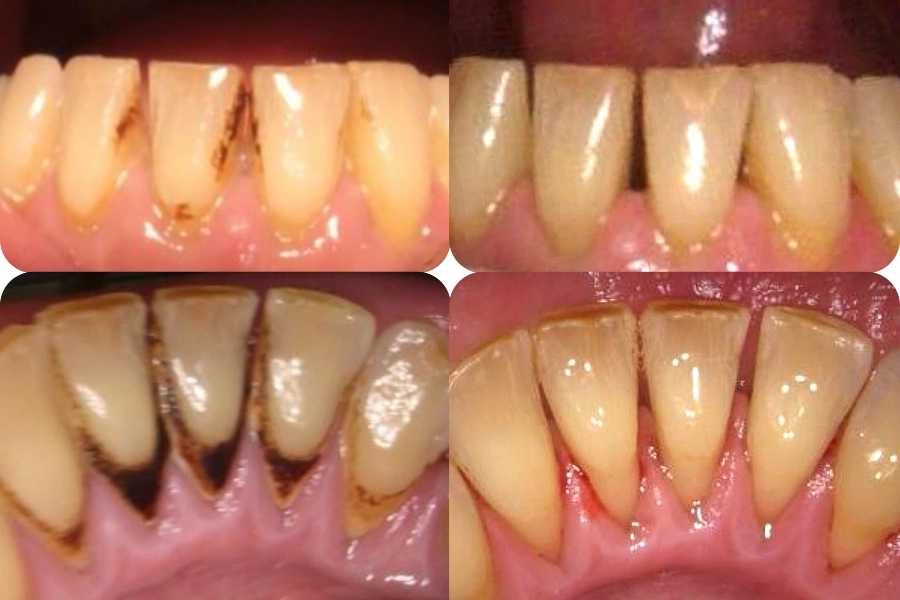

Ουλίτιδα

70€

Στίλβωση - Φθορίωση

40€